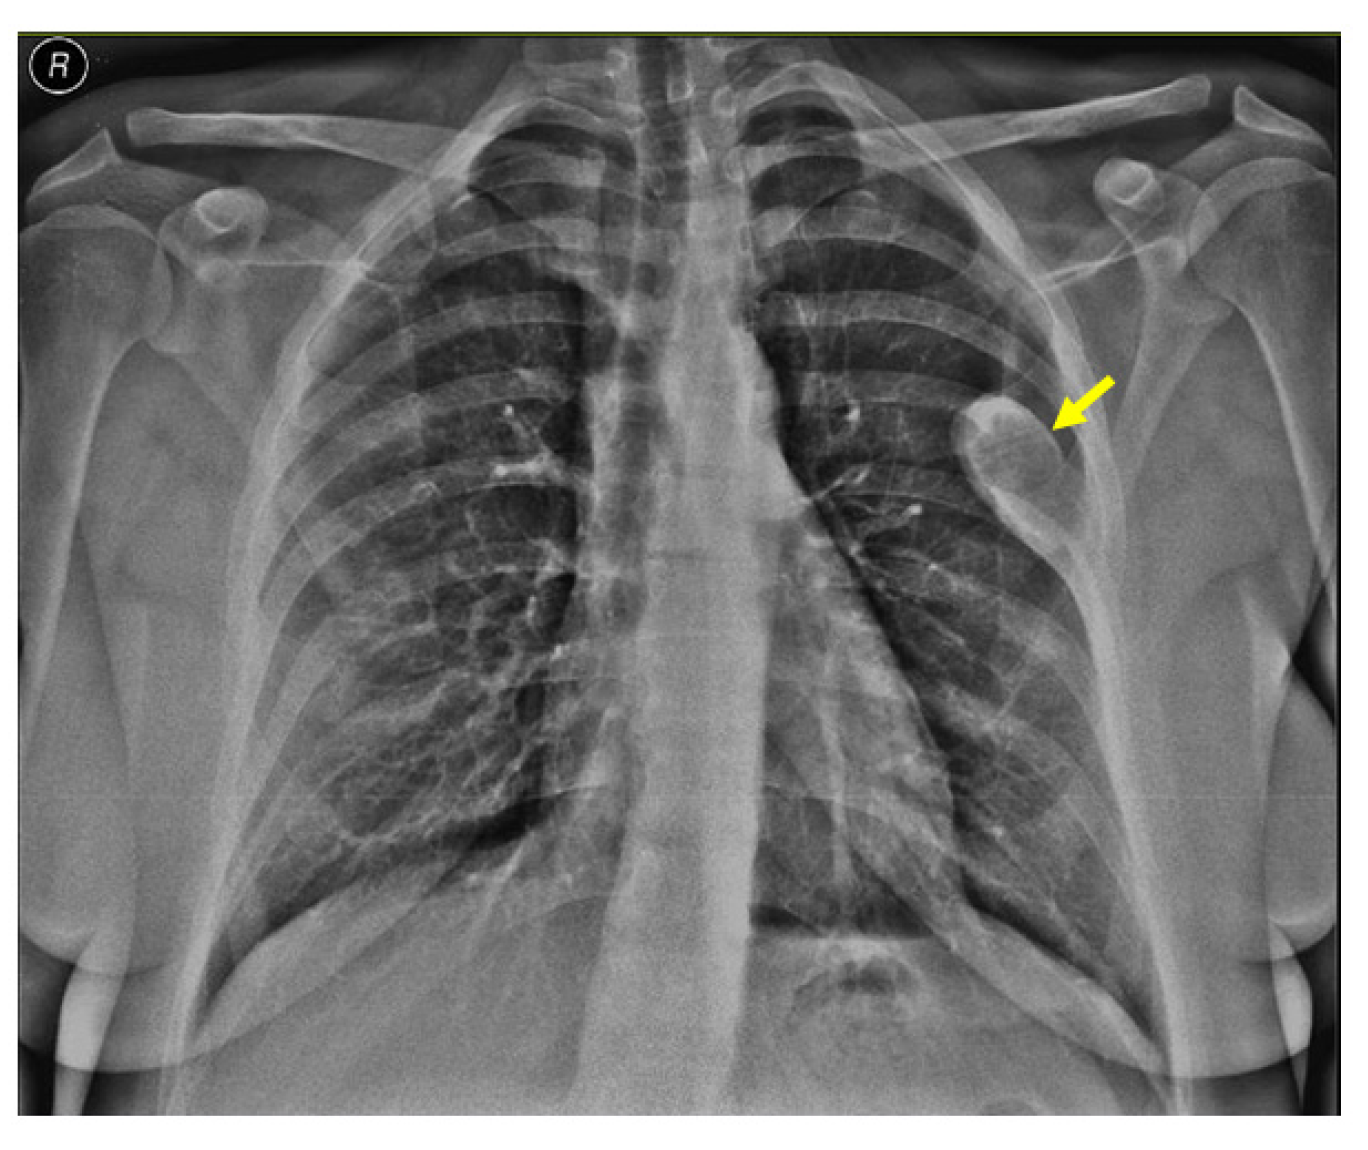

Noting the bone pain on admission, an X-ray screening was performed and showed a rib tumor suggestive of a brown tumor (a solitary, oval, well-shaped tumor of 6.4 by 2.7 cm in the lateral half of the left posterior sixth rib) (Figure 3).

Figure 3.

X-ray showing a brown tumor: a single, oval, well-shaped lesion of 6.4 by 2.7 cm in the lateral half of the left posterior sixth rib (yellow arrow).